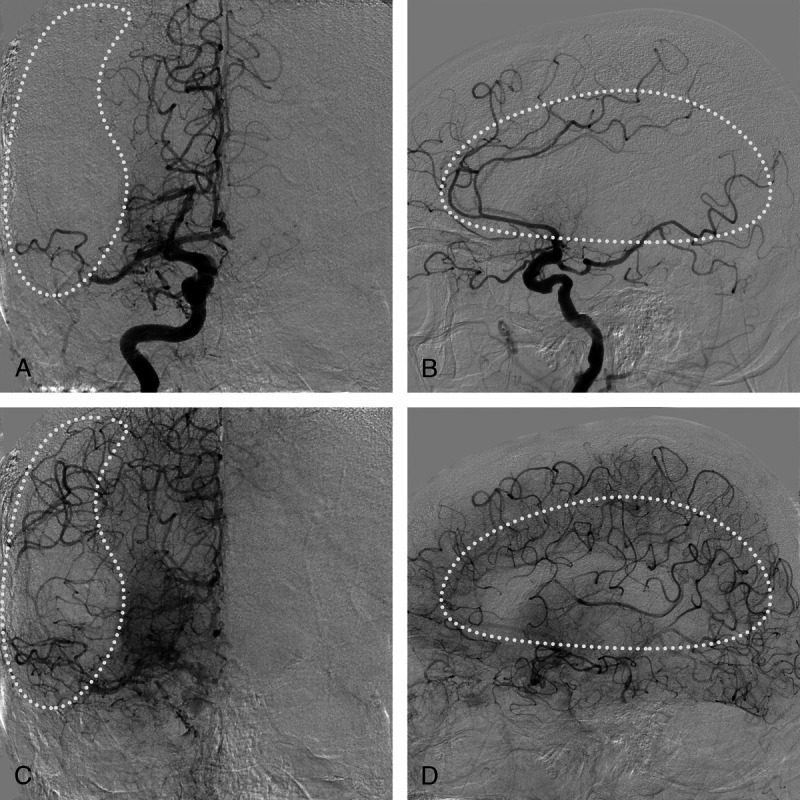

FIGURE 3.

Example case identical to the case in Figure 2. Anteroposterior (A) and lateral (B) digital subtraction angiography views in the early contrast phase are shown. Anteroposterior (C) and lateral (D) views of the late contrast phase show good filling of the collateral circulation in the middle cerebral artery territory (white dotted shapes).

Example case identical to the case in Figure 4. Anteroposterior (A) and lateral (B) digital subtraction angiography views in the early contrast phase are shown. Anteroposterior (C) and lateral (D) views of the late contrast phase show poor filling of the collateral circulation in the middle cerebral artery territory (white dotted shapes).